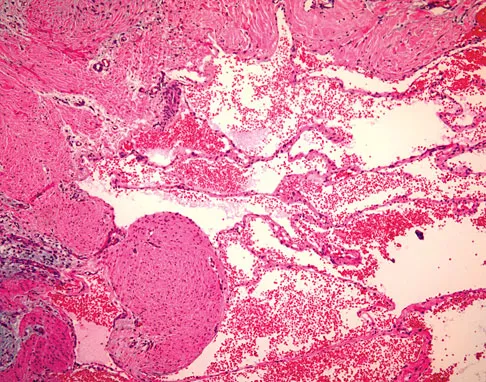

A 30-year-old patient has had severe left hip pain and difficulty ambulating, necessitating the use of a cane, for the past 6 months. A photomicrograph of the femoral head sectioned at the time of surgery is shown in Figure 31. What is the most likely diagnosis?

Explanation

The photomicrograph demonstrates a wedge-shaped infarct with femoral head collapse; therefore, the diagnosis is osteonecrosis of the femoral head. Perthes disease and osteoarthritis do not involve a wedge-shaped defect. Tuberculosis of the hip joint results in greater destruction of the articular cartilage. Basset LW, Mirra JM, Cracchiolo A III: Ischemic necrosis of the femoral head: Correlation between magnetic resonance imaging and histologic sections. Clin Orthop 1987;223:181-187.